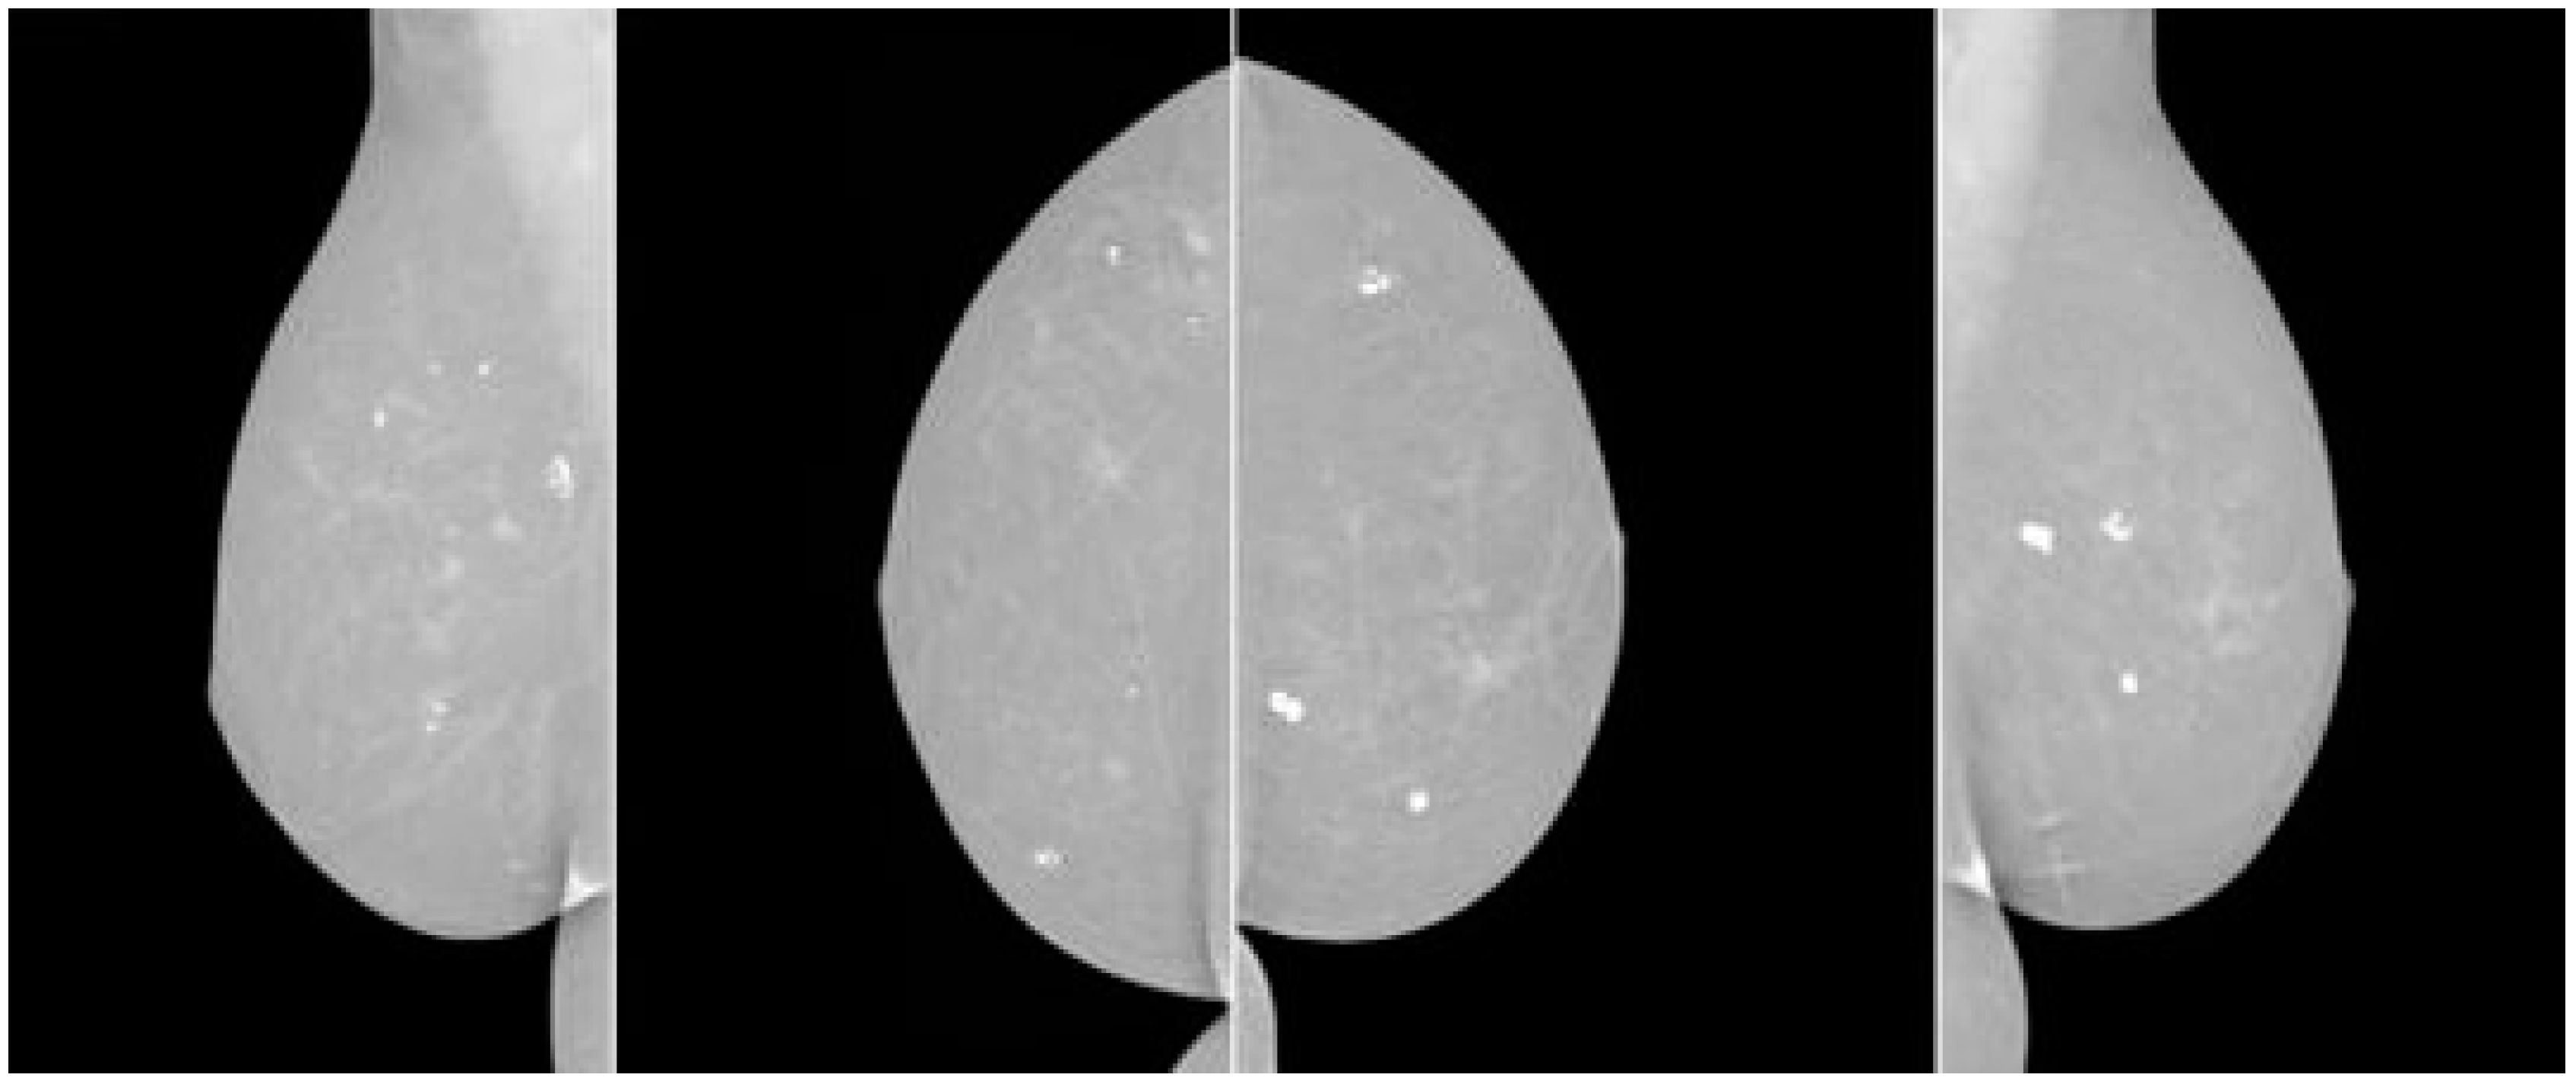

Breast cancer screening involves mammography to detect the early stages of the disease, identifying abnormalities such as tumors or microcalcifications. The procedure involves gently compressing the breast between two plates, resulting in two X-ray images. Radiologists review the images to identify suspicious findings, such as masses, abnormal densities, microcalcifications, or architectural distortions. Mammography results are often reported using the Breast Imaging Reporting and Data System (BI-RADS), which categorizes findings into levels. If a mammogram is assigned BI-RADS 0, further evaluation, such as additional imaging or a biopsy, is needed. Follow-up tests may be recommended to confirm or rule out cancer, such as ultrasound, MRI, or a breast biopsy, depending on the results and BI-RADS category.

When a mammographer examines a patient’s breast, she or he will put the breast on the mammography machine’s plate and gently compress it with a second plate to spread out the breast tissue so that the image may be taken. Each breast is X-rayed twice, once from the top down (cranio-caudal view) and once from the side (mediolateral oblique view), as is common protocol. If more views are required, that option is available.

Figure 3 shows how breast cancer on mammograms can vary depending on stage, size, and location. Radiologists examine for abnormalities and patterns to detect breast cancer. Common findings include masses, microcalcifications, architectural distortions, asymmetries, spiculated borders, and nodules. Masses, microcalcifications, and architectural distortions are early signs of breast cancer, while microcalcifications are tiny calcium deposits in breast tissue. Figure 4 show the architectural distortions. These may appear as irregularities in the breast’s structure, while asymmetries indicate differences in appearance between the left and right breasts. Speciated borders, jagged or spiky edges, and nodules are small rounded masses that are assessed for potential malignancy.

Figure 3. Breast cancer mammography screening.